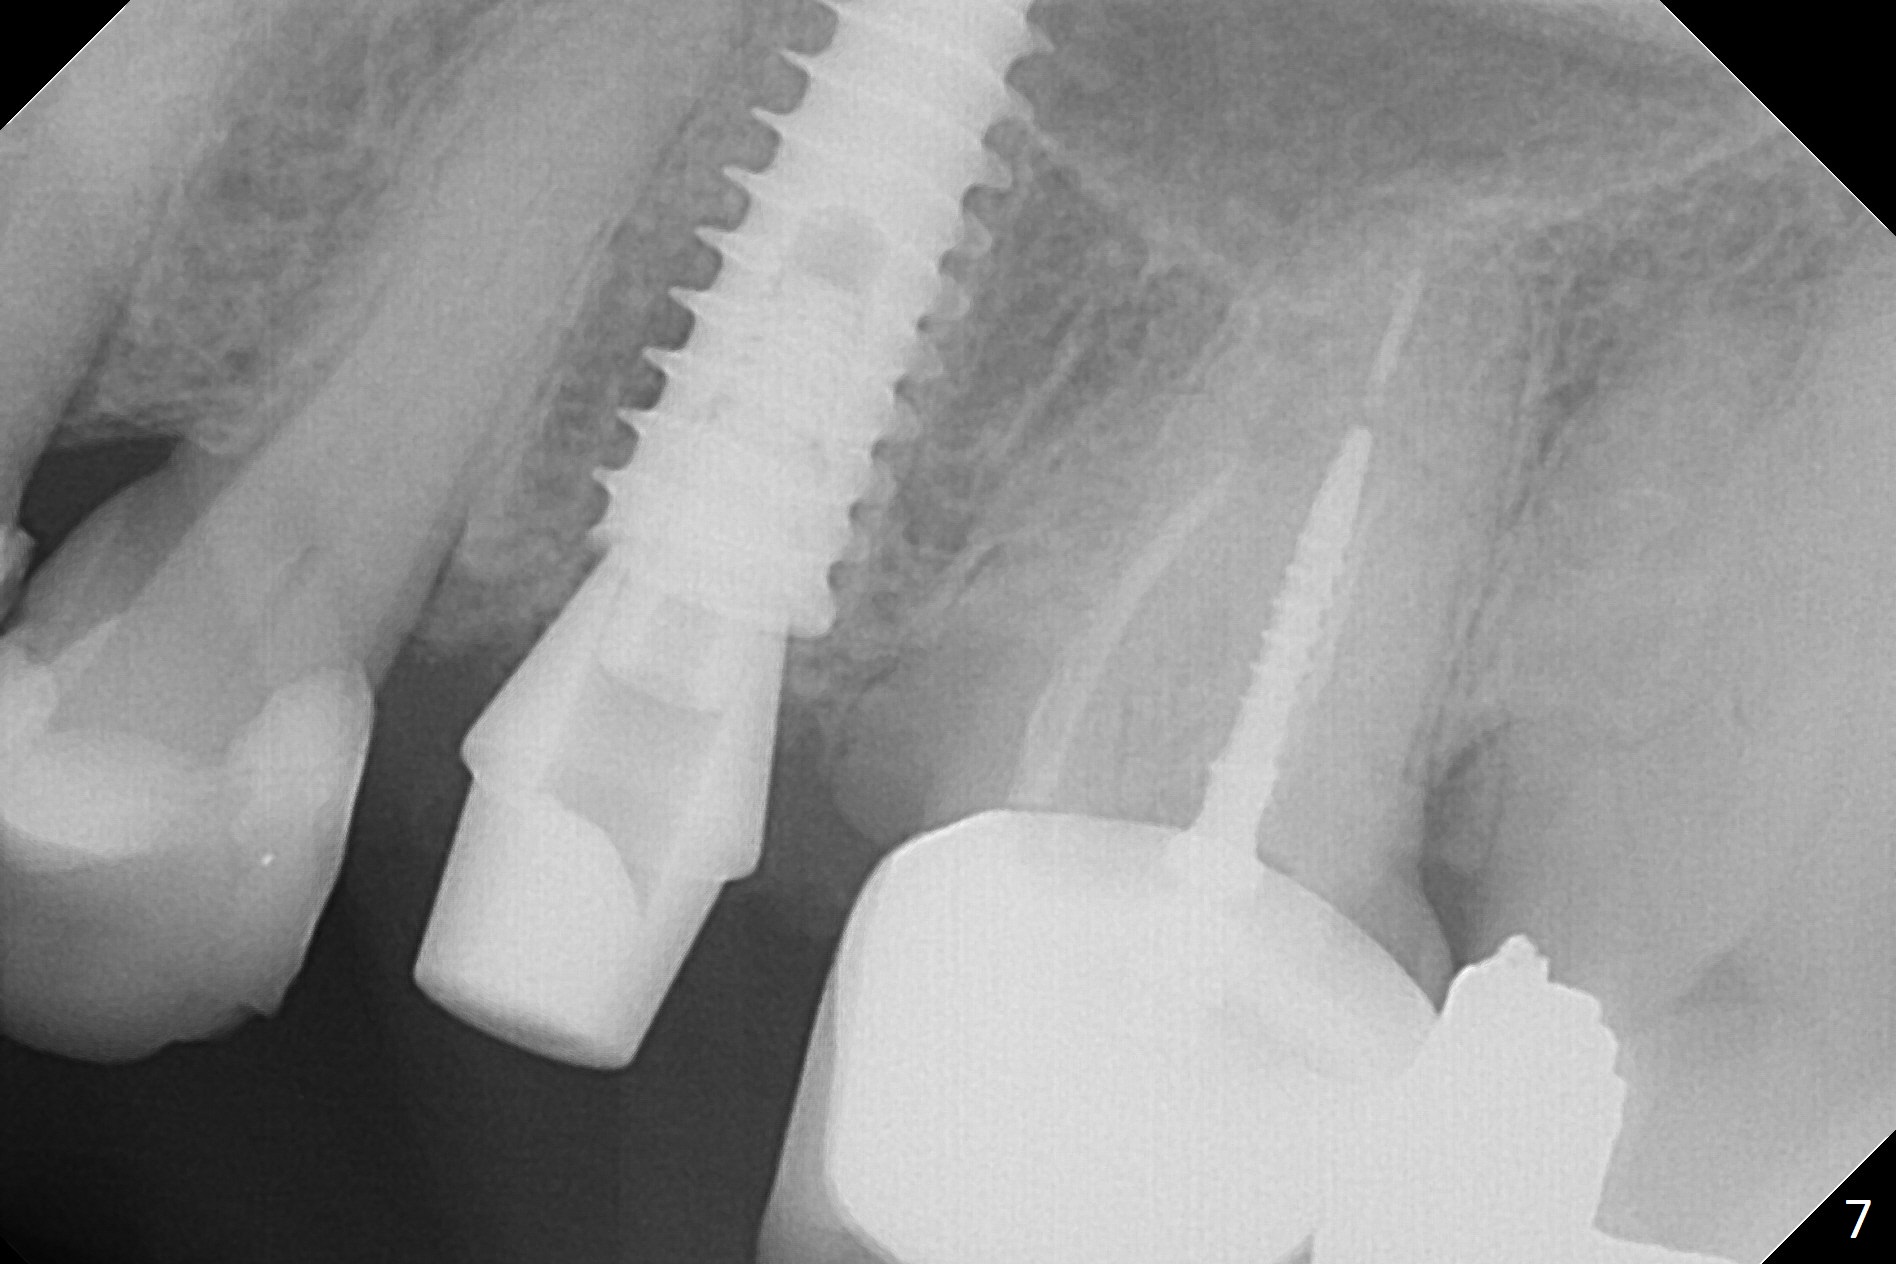

Since the apical native bone is limited at #13 after extraction, no PA is taken until a 4x11 mm dummy implant is placed after 1.6 mm and 3.3 mm drills for 13 mm (Fig.1). After using Lindamann bur to move the osteotomy distal and reusing 3.3 mm drill, the trajectory of a 4.5x11 mm IBS dummy implant improves (Fig.2,3 with low stability). When the implant is removed, the buccal portion of the socket is found to be perforated (Fig.4 P). Although the reason for the perforation is unknown, it is repaired by insertion of a piece of PRF plug, followed by allograft. #1 and 2 in Fig.4 represent the 1st and 2nd osteotomies, as shown in Fig.1 and 2, respectively. The trajectory of the final 5x13 mm implant is acceptable (Fig.5-7, different angulations), so is insertion torque (45 Ncm). After placing a 5.5x4(4) mm abutment, an immediate provisional is fabricated (Fig.8 P) with occlusal clearance (*). The interdental papillae remain in place 12 days postop (Fig.9 *). There is no sign of postop sinus infection. The provisional is loose 18 days postop; the abutment is changed to 5x4(3) mm (Fig.10). It is difficult to catch the mesial margin of the abutment for impression 4 months postop, due to poor oral hygiene and the short cuff (3 mm, Fig.11). The appointment for impression is rescheduled with emphasis on oral hygiene and no wearing the provisional for a few days prior to next appointment. Bone has grown into the space between the 1st and 2nd threads 5 months post cementation (Fig.12) and the bone is normal, solid and dense 2 years 11 months post cementation (Fig.13 >). There is mesial open margin of the tooth #14 (Fig.13,14 *).